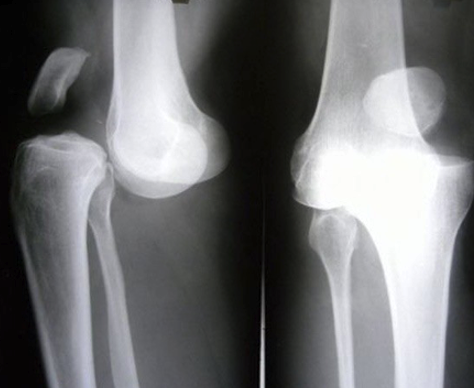

What is shown in this X-ray?

Patellar dislocation and knee dislocation